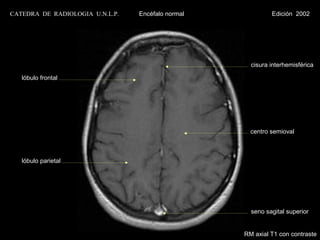

centro semioval

lóbulo frontal

tálamo                                             trígono ventricular

circunvolución

hipocampo                                          parahipocámpica

tentorio

lóbulo temporal                                    seno transverso

cerebelo

RM parasagital T2